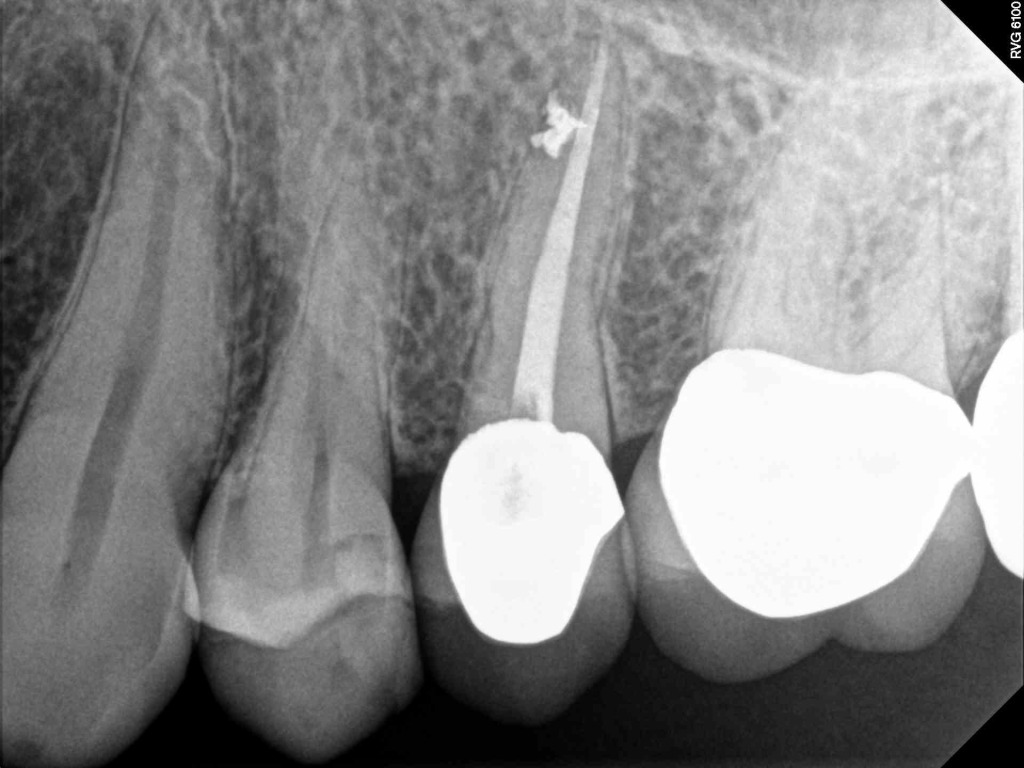

Although the primary use of visual documentation is for patient charts, dental images provide a meaningful way to communicate with patients about their care needs. Digital imagery is a vital tool for educating patients and an essential way to share information with office staff, colleagues and referring doctors. Digital technology has allowed Southcenter Endodontics to enhance our practice and improve the delivery of care to our patients. Below you will see images of “Before” and “After” scenarios. By clicking on a thumbnail image below, you will be able to see and a larger view of the x-ray taken at Southcenter Endodontics and notations made regarding each film.